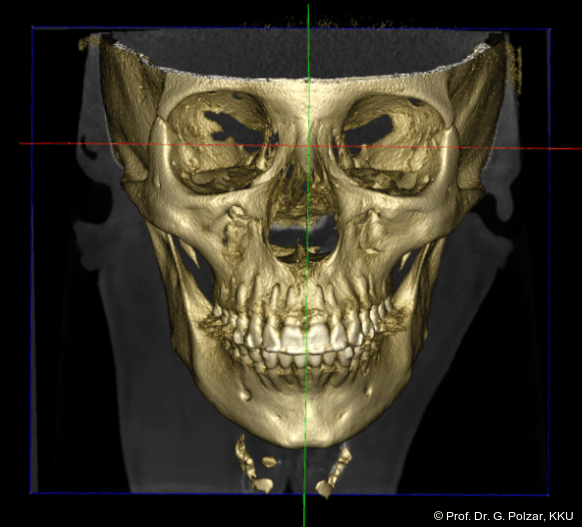

KG-Position: Die 3D-Ansicht im DVT zeigt eine vorverlagerte UK-Position bei neutraler Okklusion (Abb. 4a+b).

In der Frontalansicht ist eine leichte links-laterale Abweichung des Unterkiefers von der Schädelmitte zu erkennen (Abb. 29). Nach chirurgischer Analyse wurde die Laterognathie weitgehend ausgeglichen und der UK in CranioPlan zentrisch ausgerichtet (Abb. 30a–c).